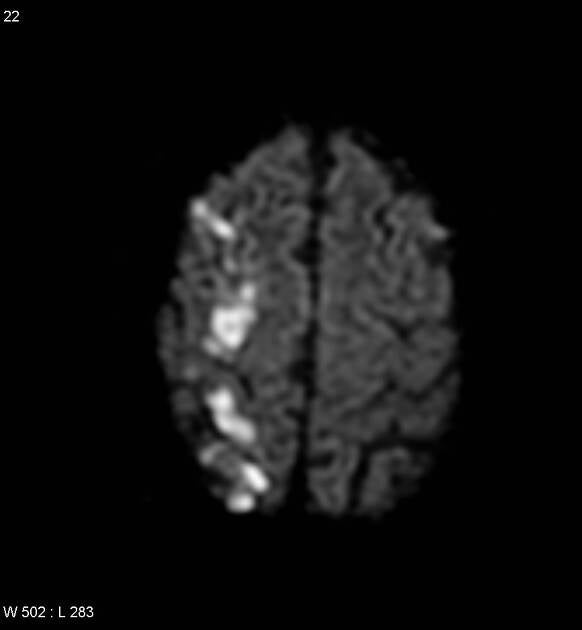

On the scans a 'rosary' pattern can often be recognized; an elongated pattern. See the images below:

Case courtesy of A.Prof Frank Gaillard, Radiopaedia.org. From the case rID: 2626 and the case rID: 5199